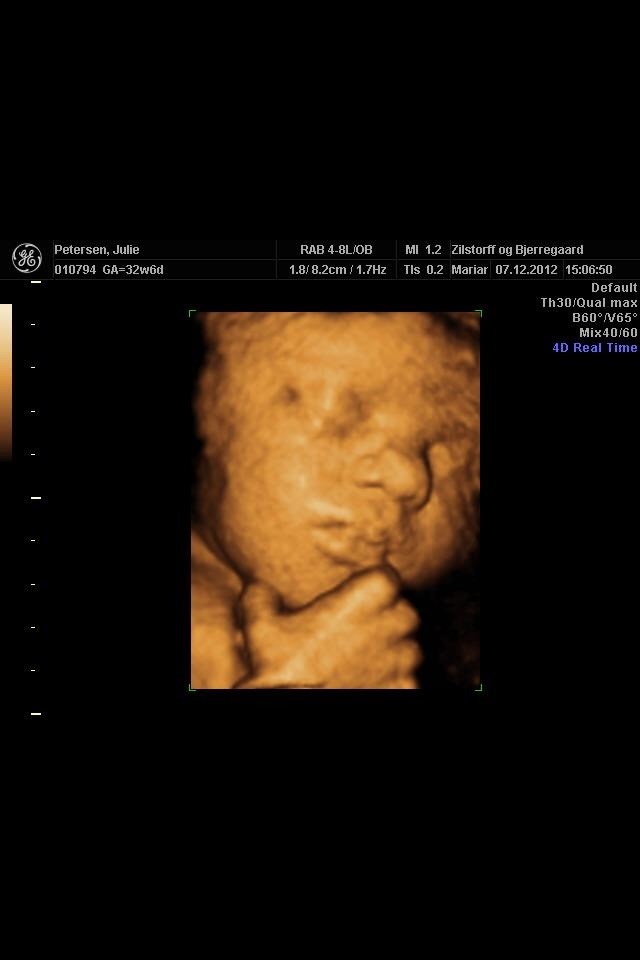

Vi købte en scanning i uge 30. Scanningsjordemoderen anbefalede uge 29 eller 30, da det skulle give det bedste resultat. Når man kommer senere hen, kan baby være så stor at det kan være svært at se noget, eller hvis den lille stiller sig tidligt fast i bækkenet, kan det være umuligt at se ansigtet (det er jo nok trods alt ikke allerede sket i uge 34). Men det er jo individuelt, det kan sagtens være, I kan få nogle fine billeder, hvis den lille ligger til det.